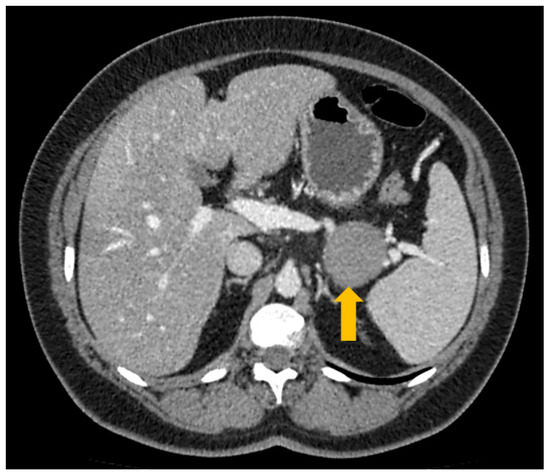

2. Case Report and Discussion